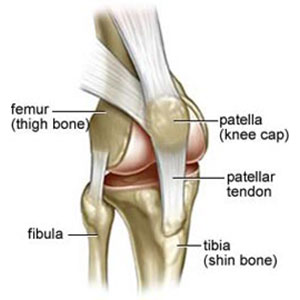

Anatomia del ginocchio

l ginocchio è un’articolazione composta essenzialmente da 3 ossa ben distinte:

- il femore

- la tibia

- la rotula o patella.

Il femore si poggia sulla parte prossimale della tibia, il piatto tibiale,tramite due strutture rotondeggianti tra loro parallele dette condili. Queste strutture articolari sono ricoperte di cartilagine, un tessuto che agisce come un vero e proprio cuscinetto; è lubrificata da un liquido molto viscoso, il liquido sinoviale, e nel mantenere separate le ossa consente un movimento fluido e con scarso attrito. Altre strutture fondamentali per un corretto funzionamento e per una lunga durata di un ginocchio sono i due menischi, laterale e mediale) che agiscono come due veri e propri ammortizzatori

I movimenti principali di un ginocchio sono la flesso-estensione, la rotazione interna ed esterna ed i movimenti laterali rispetto al proprio asse, cioè quelli in varo-valgo. Tutti questi movimenti sono resi possibili dalla presenza di 4 legamenti che hanno anche e soprattutto una funzione contenitiva per mantenere la stabilità dell’articolazione stessa: questi sono i due legamenti crociati (anteriore e posteriore) ed i due legamenti collaterali (mediale e laterale).